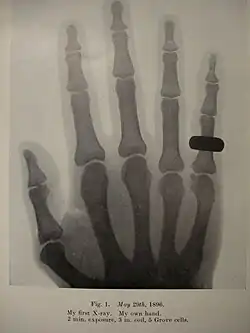

He started research on radiology in 1896, after reading about Wilhelm Röntgen's experiments in this field. Thanks to his meticulous work and advancements in his technique, Holland was able to produce radiographs that were far in advance for many years, compared to the standard practice.[3] Along with such names as Heinrich Albers-Schönberg (Germany), Antoine Béclère (France), Etienne Henrard (Belgium), Guido Holzknecht and Robert Kienböck (Austria), Thurstan Holland is considered one of the pioneers in Europe.[5]

- Holland, C. T. (1938). X rays in 1896. The British Journal of Radiology. 11(121), 1-24.